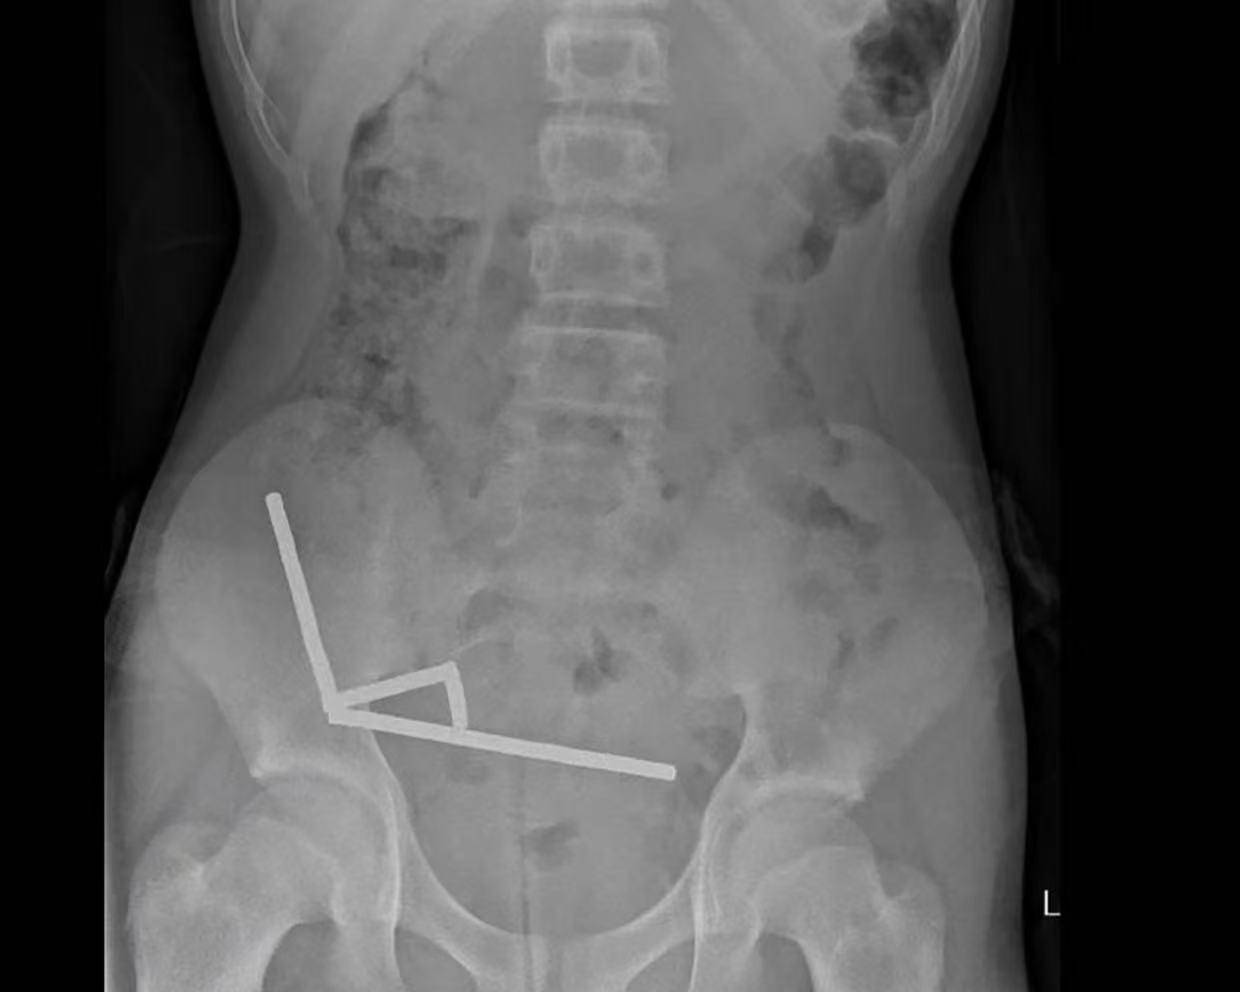

据悉,这名未透露姓名的少年在持续腹痛4天后被送往新西兰北岛的一家医院。医生通过X光检查发现,这些磁铁在他的肠道内互相吸附,形成了四条链状结构。

▲X光显示,磁铁在男孩体内紧密吸附成链状结构